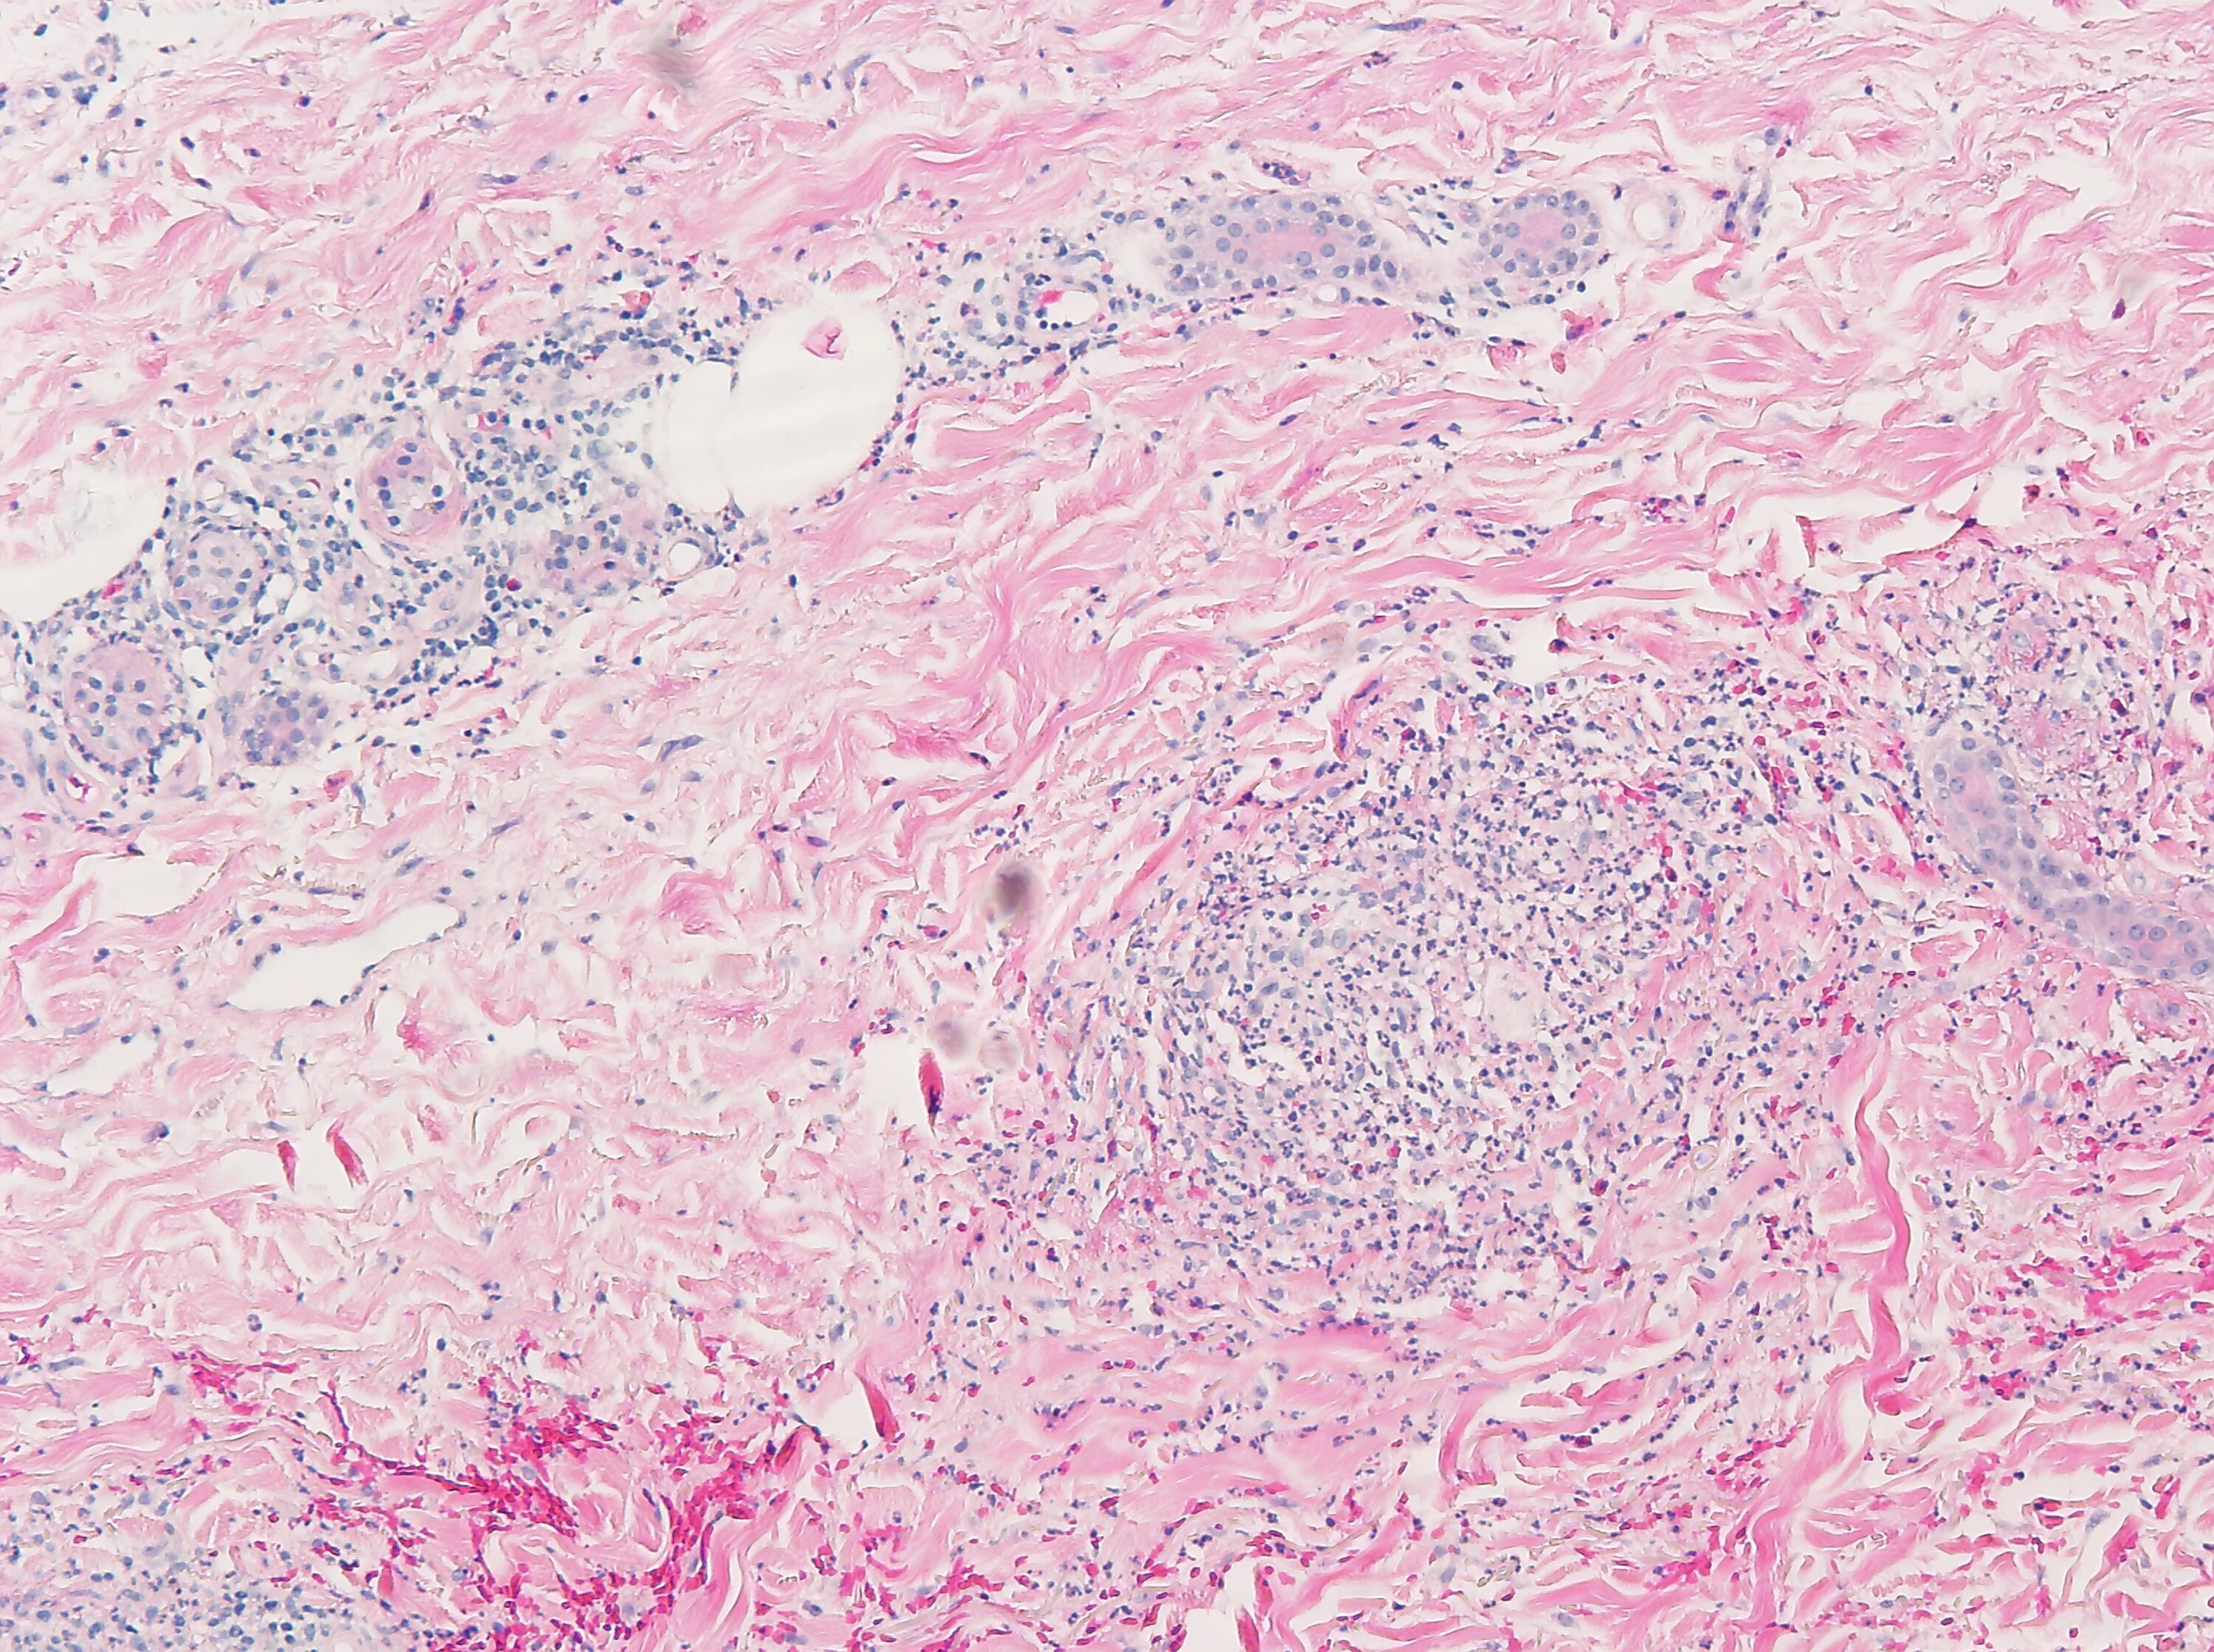

Патанат